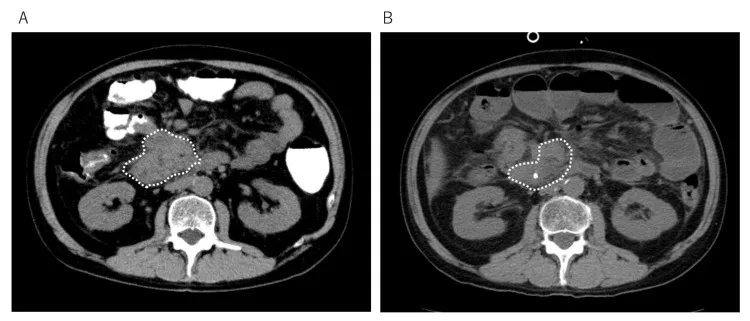

治疗效果呈现明确获益:CT检查显示,治疗前患者右下肺原发病灶伴胸腔积液,治疗114天后原发灶几乎消失;治疗第213天时虽出现复发迹象,但338天后复查可见复发灶缩小(详见下图)。

▲图源“Cureus”,版权归作者所有,如无意中侵犯了知识产权,请联系我们删除